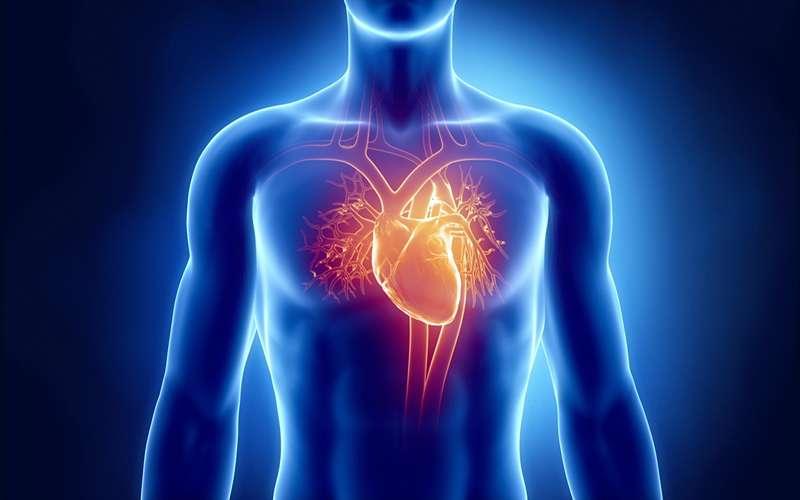

علائم فشار خون بالا و ارتباط آن با بیماریهای قلبی

۳۲درصد جمعیت بالای ۱۸ سال در ایران به فشار خون بالا دچارند. این بیماری عوارض ناخوشایندی دارد و شبیه یک قاتل خاموش است که بیسروصدا، ابتدا فرصت یک زندگی سالم …